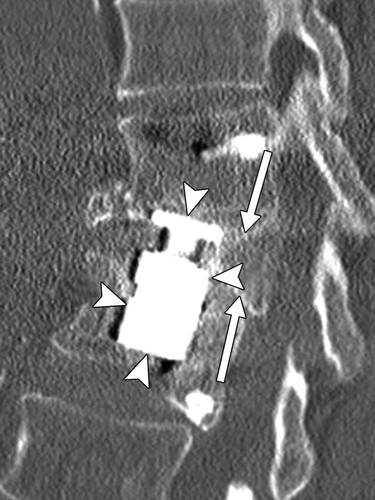

图5A-67岁男子L3-L5腰椎融合3年后复发性左侧放射性疼痛。MDCT图像显示左侧椎弓根螺钉(L3-L5)。 左L5-S1神经孔被表示盘或瘢痕组织的软组织阻塞,L5神经根被压缩(薄箭头)。 L2-L3和L5-S1中的真空现象(粗箭头),表示髓核变性。